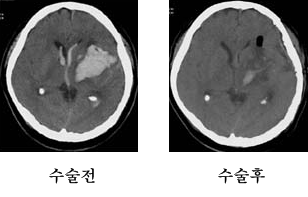

일반적으로 고혈압 환자에게 흔히 발생하는데 뇌혈관중 미세혈관이 터져 뇌를 압박합니다. 주로 활동하는 낮에 발생하며 의식혼탁과 편마비를 동반하는 경우가 많습니다. 진단은 뇌 컴퓨터 단층 촬영(CT)으로 쉽게 진단이 됩니다.

출혈된 위치와 양에 따라 증상이 다양하게 나타나며 출혈된 양이 30~40cc 이하이면 수술하지 않고 약물 요법을 권장합니다. 대부분 터진혈종은 약 3주안에 스스로 서서히 흡수되기 때문입니다. 그러나 양이 많은 경우는 응급개두술을 시행하여 혈종을 제거해 주어야 합니다.